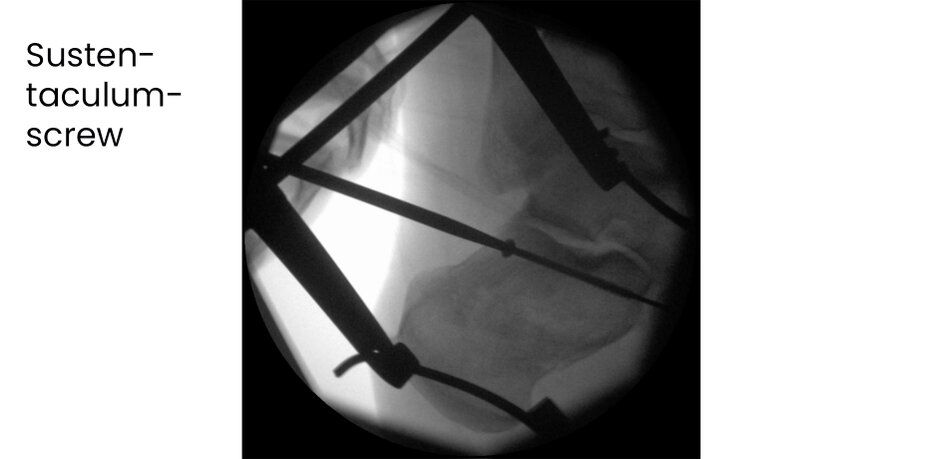

Case 17KL, male, 35y, surgery on day of trauma